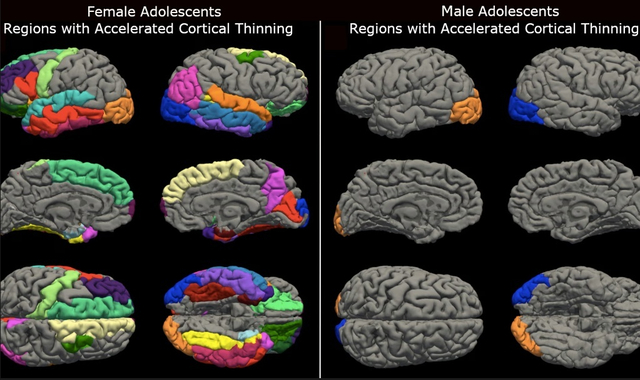

A koronavírus-járvány idején a lezárások mindenkit egyformán érintettek, úgy tűnik azonban, hogy nem mindenkinél járt ugyanolyan következménnyel a dolog. Az amerikai Washington Egyetem kutatói MRI-vizsgálatok alapján azt találták, hogy mind a serdülő fiúk, mind pedig a serdülő lányok agya a korai öregedés jeleit mutatta, utóbbiakra azonban sokkal rosszabb hatással volt a lezárás.

A The Guardian beszámolója szerint míg a fiúk esetében az átlagos öregedés 1,4 év volt, addig a lányoknál 4,2 évről lehet beszélni. Hogy mindennek van-e valamilyen negatív hatása, nem tudni, arra viszont felhívják a figyelmet, hogy a lezárás hatással lehetett a fiatalok mentális egészségére és a tanulási képességeikre.

A csapat 2021-ben és 2022-ben újra meglátogatta ugyanazt a csoportot – ekkor már túl volt a világ a lezáráson –, és további MRI-felvételeket készített az aktuálisan 12 és 16 év közötti korosztály agyáról. A pandémia előtti agyfejlődéshez képest a fiúk agyának egyik területe a felgyorsult kéregvékonyodás jeleit mutatta, és ez volt megfigyelhető a lányoknál is, mindkét agyfélteke és minden lebeny esetében.

A szakemberek tanulmánya – amely a Proceedings of the National Academy of Sciences tudományos lapban jelent meg – az első, amely szembetűnő különbségeket mutat a fiúk és a lányok agya között.

Az agy öregedése mindkét nemnél megfigyelhető volt, ami befolyásolja az arcok meg- és felismerését, a lányoknál azonban ez erőteljesebb volt. A szakemberek szerint az érintett területek közül több

- az érzelmek feldolgozásának,

- az arckifejezések értelmezésének, valamint

- a nyelvi megértésnek

az alapját jelenti, amelyek a kutatók szerint a kommunikáció szempontjából kritikus fontosságúak.

Kuhl szerint a különbség azt tükrözi, hogy a lányok sokkal inkább függnek a társadalmi csoportoktól és interakcióktól – sokkal többet beszélnek az érzelmeikről, és általában véve is többet beszélgetnek, így a jóllétük, valamint az idegi, fizikai és mentális egészségük is sokkal jobban függ a társadalmi csoportoktól.

A szakember szerint további vizsgálatokra van szükség annak megállapítására, hogy az agy öregedése befolyásolja-e a kognitív teljesítményt, ugyanakkor hangsúlyozza, hogy az agykéreg elvékonyodása összefügghet a serdülőkori élet nehézségeivel, és a neuropszichiátriai rendellenességek nagyobb kockázatát rejtheti.